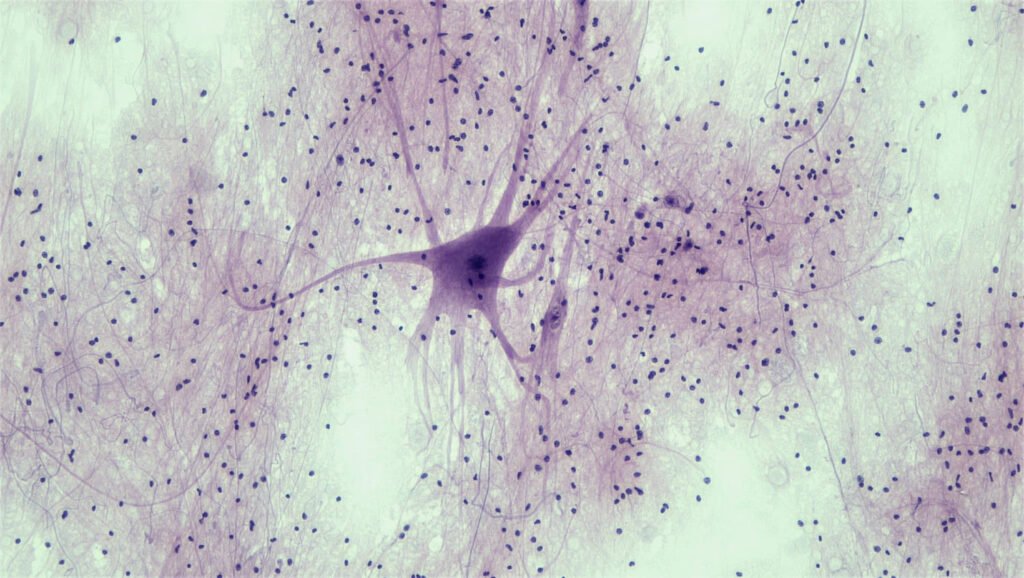

Evidence of Neurogenesis

Observations over the years have challenged this view. In the 1980s, studies on canaries revealed seasonal growth and loss of neurons in brain regions controlling singing, indicating that the adult brain can generate new neurons.